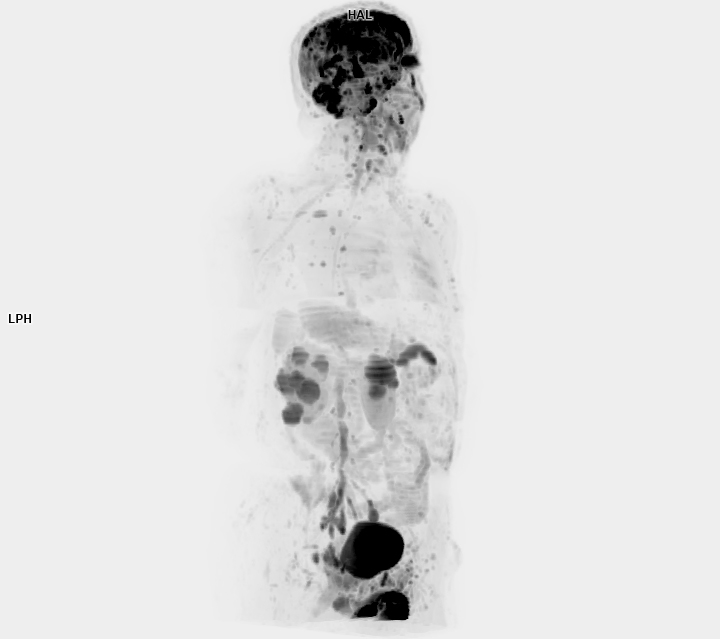

• 3 TESLA MR ÇEKİM GÖRÜNTÜLERİ

3 Tesla MR Çekim Görüntüleri

• 3 Tesla MR Çekim Görüntüleri